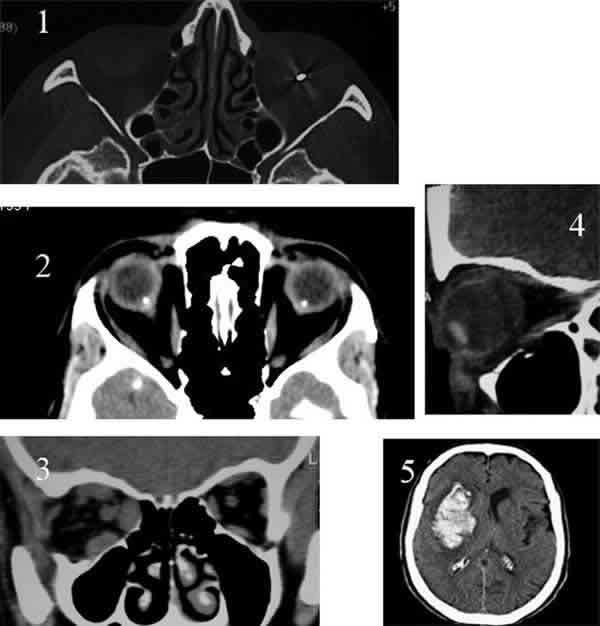

Fig. 2: En esta comparativa, se aprecia el distinto aspecto que tienen las

secuencias más frecuentemente utilizadas. Las tres primeras imágenes

corresponden a un meningioma del nervio óptico. En T1 la grasa orbitaria aparece

brillante y el vítreo oscuro. La secuencia T1 da una imagen más anatómica que

T2. En T2 por el contrario el vítreo aparece brillante y la grasa da una señal

baja. La secuencia T2 resulta de gran utilidad para poner de manifiesto la

patología. Como puede apreciarse en T2 el tumor es más evidente. La cuarta

imagen corresponde a una secuencia FLAIR, esta secuencia es de elección para la

detección de patología desmielinizante.